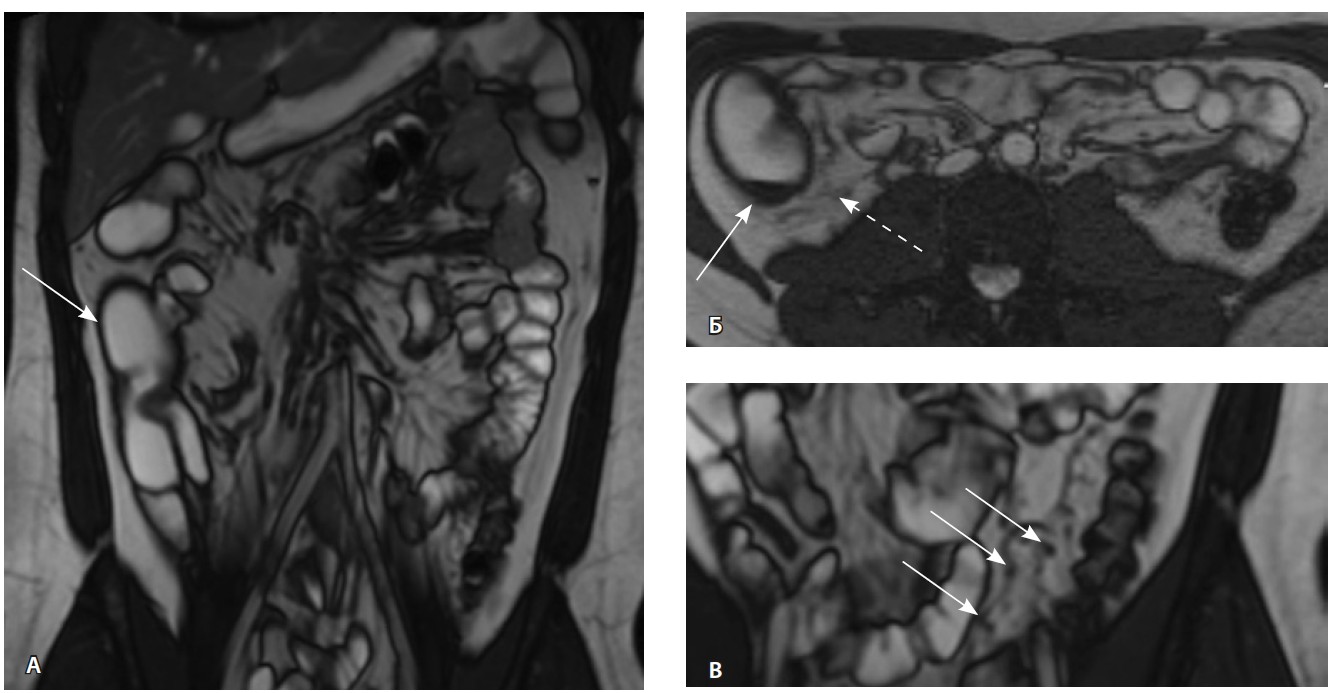

Одним из условий проведения процедуры ВИСТ-АТГСК было отсутствие септических очагов, в связи с чем выполнено углубленное исследование перианальных поражений БК. По данным магнитнорезонансной томографии органов малого таза выявлен простой аноректальный свищ. За месяц до начала режима кондиционирования проведена санация параректального свища (установка дренажа-сетона), тогда же выполнено последнее п/к введение препарата устекинумаб. По данным контрольной илеоколоноскопии подтверждена активность болезни (рис. 4).

Рис. 4. Контрольная илеоколоноскопия. Слизистая оболочка толстой кишки с изменениями: А – щелевидные и полигональные эрозии (стрелка), Б – поверхностная язва диаметром до 0,5 см (стрелка)